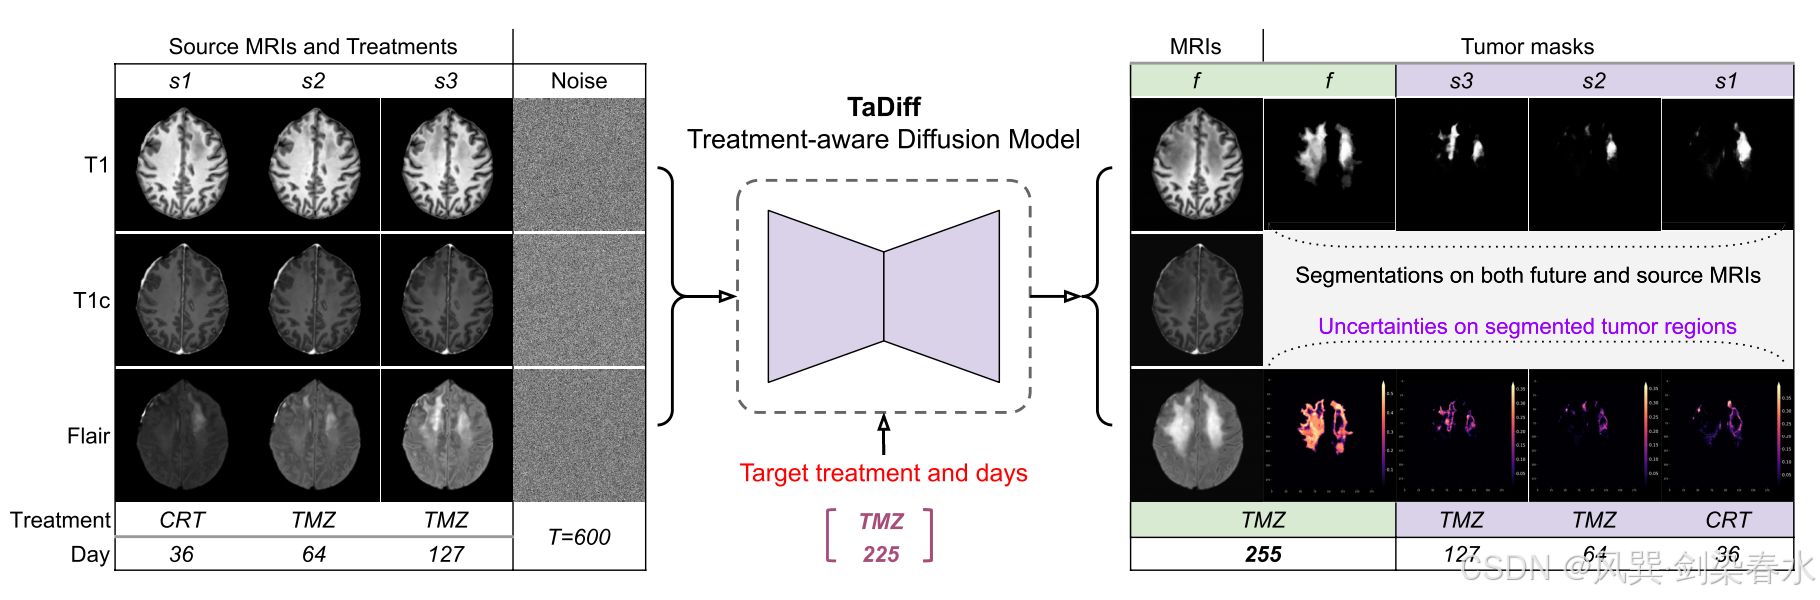

Figure 1 | TaDiff 模型概述(treatment-aware diffusion probabilistic model,治疗感知扩散概率模型):该方法旨在为任何给定的目标或未来治疗(如替莫唑胺)及时间点(如第225天),生成一组合成的 MRI 图像和肿瘤进展掩模,这些掩模基于源序列 MRI(如s1、s2 和 s3)和治疗方案(如第36天的放化疗,第64天和127天的替莫唑胺);

Figure 2 | 针对任何给定的治疗信息和目标/未来时间点,用于多参数MRI生成和肿瘤生长预测的 TaDiff 模型端到端管道:该模型以条件源 MRI 序列和治疗感知嵌入作为输入,输出目标/未来的 MRI 图像,并同时预测源治疗日点和给定的目标治疗日点的肿瘤掩模;